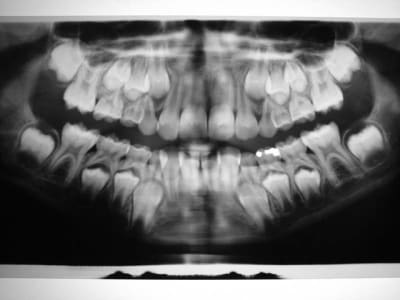

Avant TTT.

à suivre Bjc.

1 k41u2c - Eugenol

2 uwoszw - Eugenol

3 fen5h1 - Eugenol